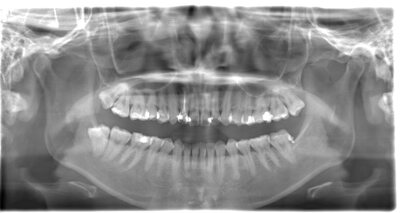

抜歯後

事前にCT撮影を行い神経との位置関係を確認して抜歯を行いました。右下親知らずは歯ぐきの中に完全に埋まり、

また斜めに生えていた為歯ぐきを切って親知らずの頭部分を分割して抜きました。

翌日多少の腫れが見られましたが痛みも痛み止めを飲めば過ごせる程度で出血はほとんどありませんでした。

基本情報

| 年齢・性別 | 24歳・女性 |

|---|---|

| 主訴 | 右下の親知らずが抜きたい |

| 治療内容 | 完全埋伏抜歯 |

| 治療期間 | 60分 |

| 治療費 | 約8,000円 |

| リスク・副作用 | 2〜3日は腫れと痛みがある。 必要に応じて抜歯を2回に分けて行う場合がある。 |